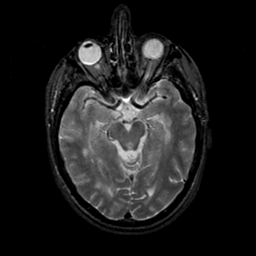

MR Study #23, January 26, 1992 -- Slice #20